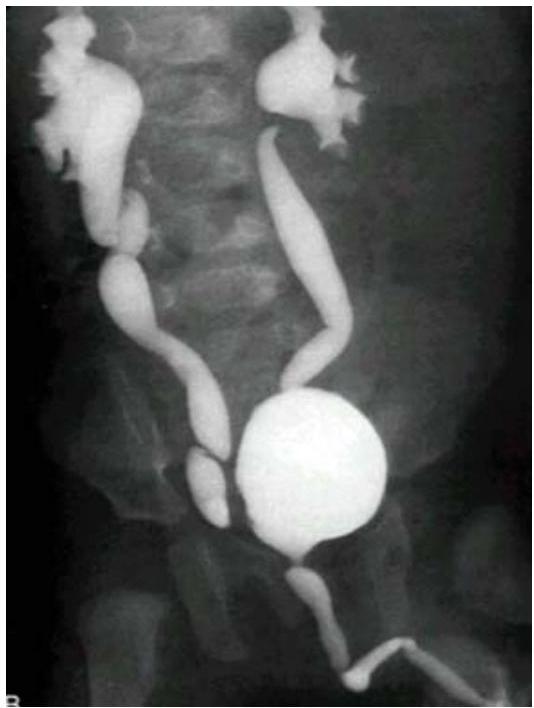

Posterior Urethral Valve (PUV)

Modality:

- MCUG / VCUG (voiding cystourethrogram) only in boys

Findings:

- Dilated proximal urethra

- Dilated ureter

- Dilated bladder

- Dilated posterior urethra

Can be diagnosed antenatal and prevented!

Complications:

- Renal failure

- UTI

Treatment:

- Surgical removal of the valve

- Catheter or drain procedure as temporary measure

Vesicoureteral Reflux (VUR) — MCUG/VCUG

Scenario: Infant referred for evaluation following recurrent UTI.

Investigation? Micturating cystourethrogram (MCUG) / Voiding cystourethrogram (VCUG)

Findings?

- Posterior urethral valve

- Dilated ureters and bladder

- Tortuous ureters

- Dilated renal pelvis and calyces bilaterally (hydronephrosis)

Diagnosis? Vesicoureteral Reflux (VUR) — grade 4-5.